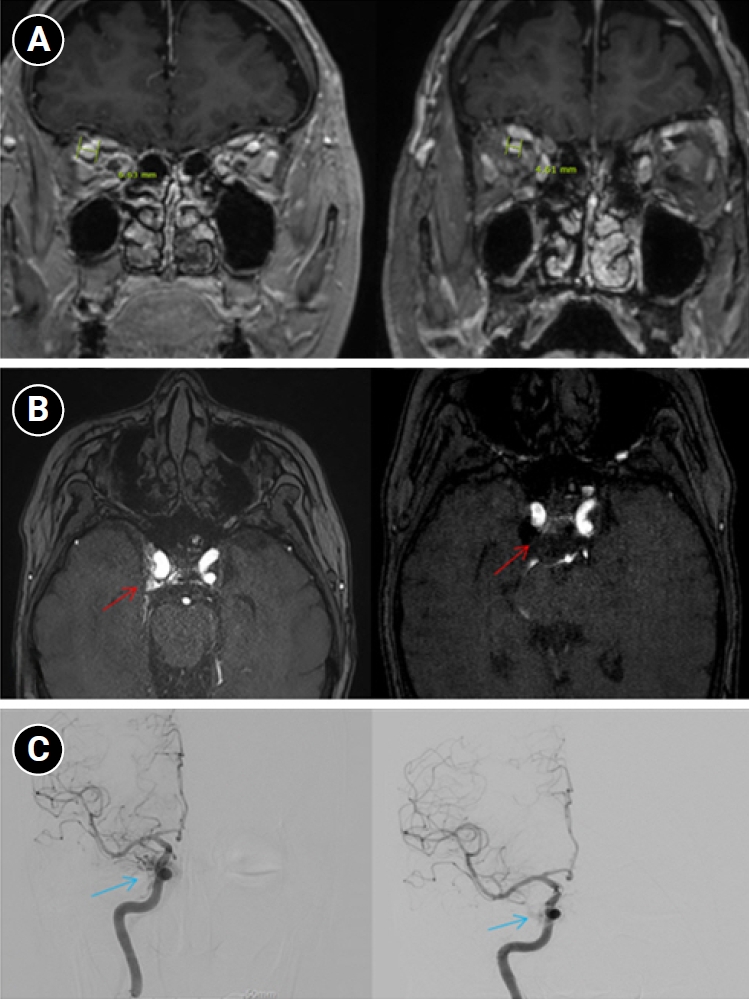

Baseline hematology and chemistry—including complete blood count, electrolytes, renal/hepatic indices—and coagulation tests (prothrombin time/international normalized ratio, activated partial thromboplastin time) were within reference limits. Erythrocyte sedimentation rate and C-reactive protein were normal. A focused screen for secondary trigeminal neuropathy (thyroid-stimulating hormone, vitamin B12, HbA1c) was negative. There were no clinical signs of infection. Brain magnetic resonance imaging (MRI) demonstrated high flow related signal in the right cavernous sinus and asymmetric dilation of the superior ophthalmic veins (right>left), raising suspicion for a CCF (Figure 1). Definitive diagnosis was established on digital subtraction angiography (DSA), which identified a right CCF. DSA demonstrated an indirect CCF supplied by the right meningohypophyseal trunk of the ICA and by right ECA branches, including the internal maxillary artery and the cavernous branch of the middle meningeal artery, consistent with Barrow type D (Figure 2).6 Barrow type D denotes an indirect, low-flow fistula with dual ICA/ECA dural supply; unlike direct type, indirect types present more insidiously, and symptom patterns are largely determined by venous drainage, with posterior drainage often manifesting as CN VI palsy and headache (Table 1).1,3,6,7 The fistula was treated with transvenous Onyx embolization. On post-procedure day 1, non-contrast time-of-flight magnetic resonance angiography (TOF-MRA) demonstrated a marked reduction of flow related hyperintensity within the right cavernous sinus, and the right superior ophthalmic vein caliber decreased from 6.63 to 4.61 mm (Figure 3A, B). Follow-up DSA (at 3 weeks) likewise showed substantial attenuation of fistulous opacification (Figure 3C), supporting a significant interval decrease in arteriovenous shunting. At 1–2 weeks, the patient reported an ~80%–90% reduction in dental/lower-facial pain and bifrontal headache from NRS 7–8 to 1–2. By 1 month, red-glass testing demonstrated resolution of primary-position diplopia. Formal prism measurements were unavailable; bedside ocular-motor grading was recorded using a standard duction underaction scale (–4 to 0). Right abduction improved from –1 to 0, and primary-position diplopia was absent at distance and near, consistent with recovery from abducens palsy.

Figure 1.Brain magnetic resonance imaging (MRI) findings. (A, B) Non-contrast time-of-flight magnetic resonance angiography shows a high flow-related signal (red arrows) within the right cavernous sinus. (C) Contrast-enhanced T1-weighted MRI demonstrates asymmetric dilation of the superior ophthalmic veins (blue arrow), more prominent on the right.

Figure 3.Imaging changes before and after embolization. (A) Brain magnetic resonance imaging (coronal section through the orbits) shows a decrease in the diameter of the right superior ophthalmic vein from 6.63 mm pre-embolization to 4.61 mm post-embolization, indicating reduced venous congestion. (B) Axial time-of-flight magnetic resonance angiography demonstrates that flow-related hyperintensity within the right cavernous sinus is markedly reduced after embolization (red arrows), consistent with decreased shunt flow. (C) Digital subtraction angiography images before embolization show abnormal early pericavernous venous filling along the right cavernous sinus region (blue arrows), compatible with carotid-cavernous shunting. On follow-up, this abnormal filling is no longer visualized, consistent with interval reduction in shunt flow.